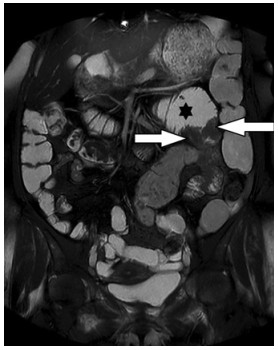

Abstract: Gastrointestinal mast cell sarcoma is a rare variant of mastocytosis. It is a unifocal tumor with high destructive capacity and metastatic potential. Diagnosis of mast cell sarcoma can be challenging and might be so delayed that unfavorable prognosis may be expected. In this case report, we will describe our experience with a case of mast cell sarcoma in the small intestine of an elderly woman, which was diagnosed early on throughout the course of her disease and successfully treated. The patient was a 59-year-old woman who presented with abdominal pain, flushing, weight loss, and vomiting. Imaging studies supported the existence of an infiltrative neoplasm in the jejunum. Then, surgical removal of the tumor was performed. The presence of mast cells in the resected tumor was confirmed by immunohistochemistry, histopathology, and Giemsa staining. After almost a year of follow-up, the patient’s overall condition was fine, and no signs of recurrence were found. This is the first reported case of successfully treated gastrointestinal mast cell sarcoma. All of the previously reported cases had been diagnosed after recurrence with no response to treatment. Our case shows the significance of early diagnosis and treatment in this condition and its impact on outcome and prognosis. That could be achieved only if the pathologist has a high suspicion for this rare disease and keeps it in the back of one’s mind.